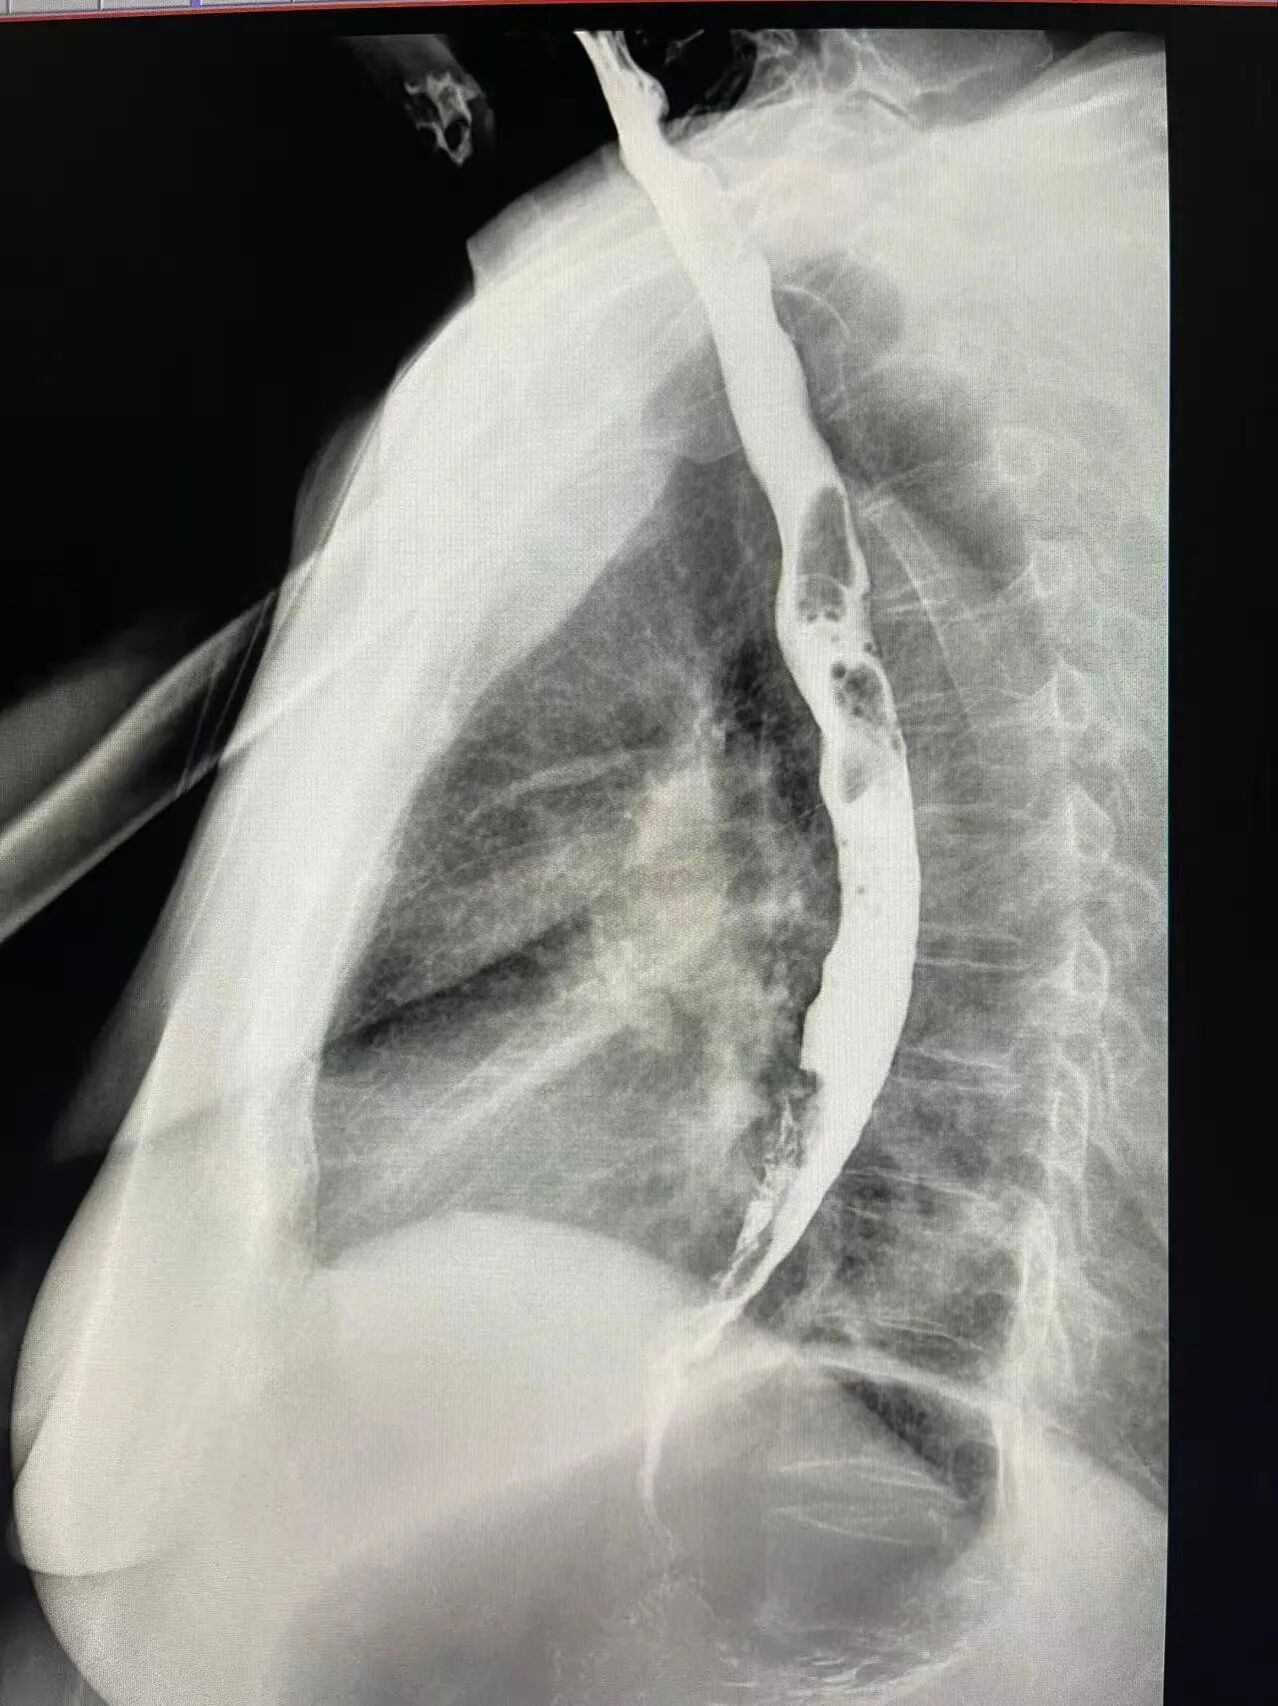

其实,除了胃镜、肠镜,还有一种无痛、无创、舒适、安全的检查方式“消化道钡餐造影”。它不用插管、不用麻醉,喝一杯“白色药水”,在X线透视下,钡剂如同“白色造影剂”均匀涂布在消化道黏膜上,通过多角度、多时相的动态观察,医生不仅能发现微小的黏膜病变,还能实时评估胃肠的蠕动能力和排空功能。

我院引进的数字化胃肠机,结合传统的钡餐造影技术,能够动态、清晰地观察消化道器质性病变和功能性改变,尤其对于胃溃疡、慢性胃炎、十二指肠憩室、消化道肿瘤以及胃下垂等功能性疾病的诊断具有重要临床价值。